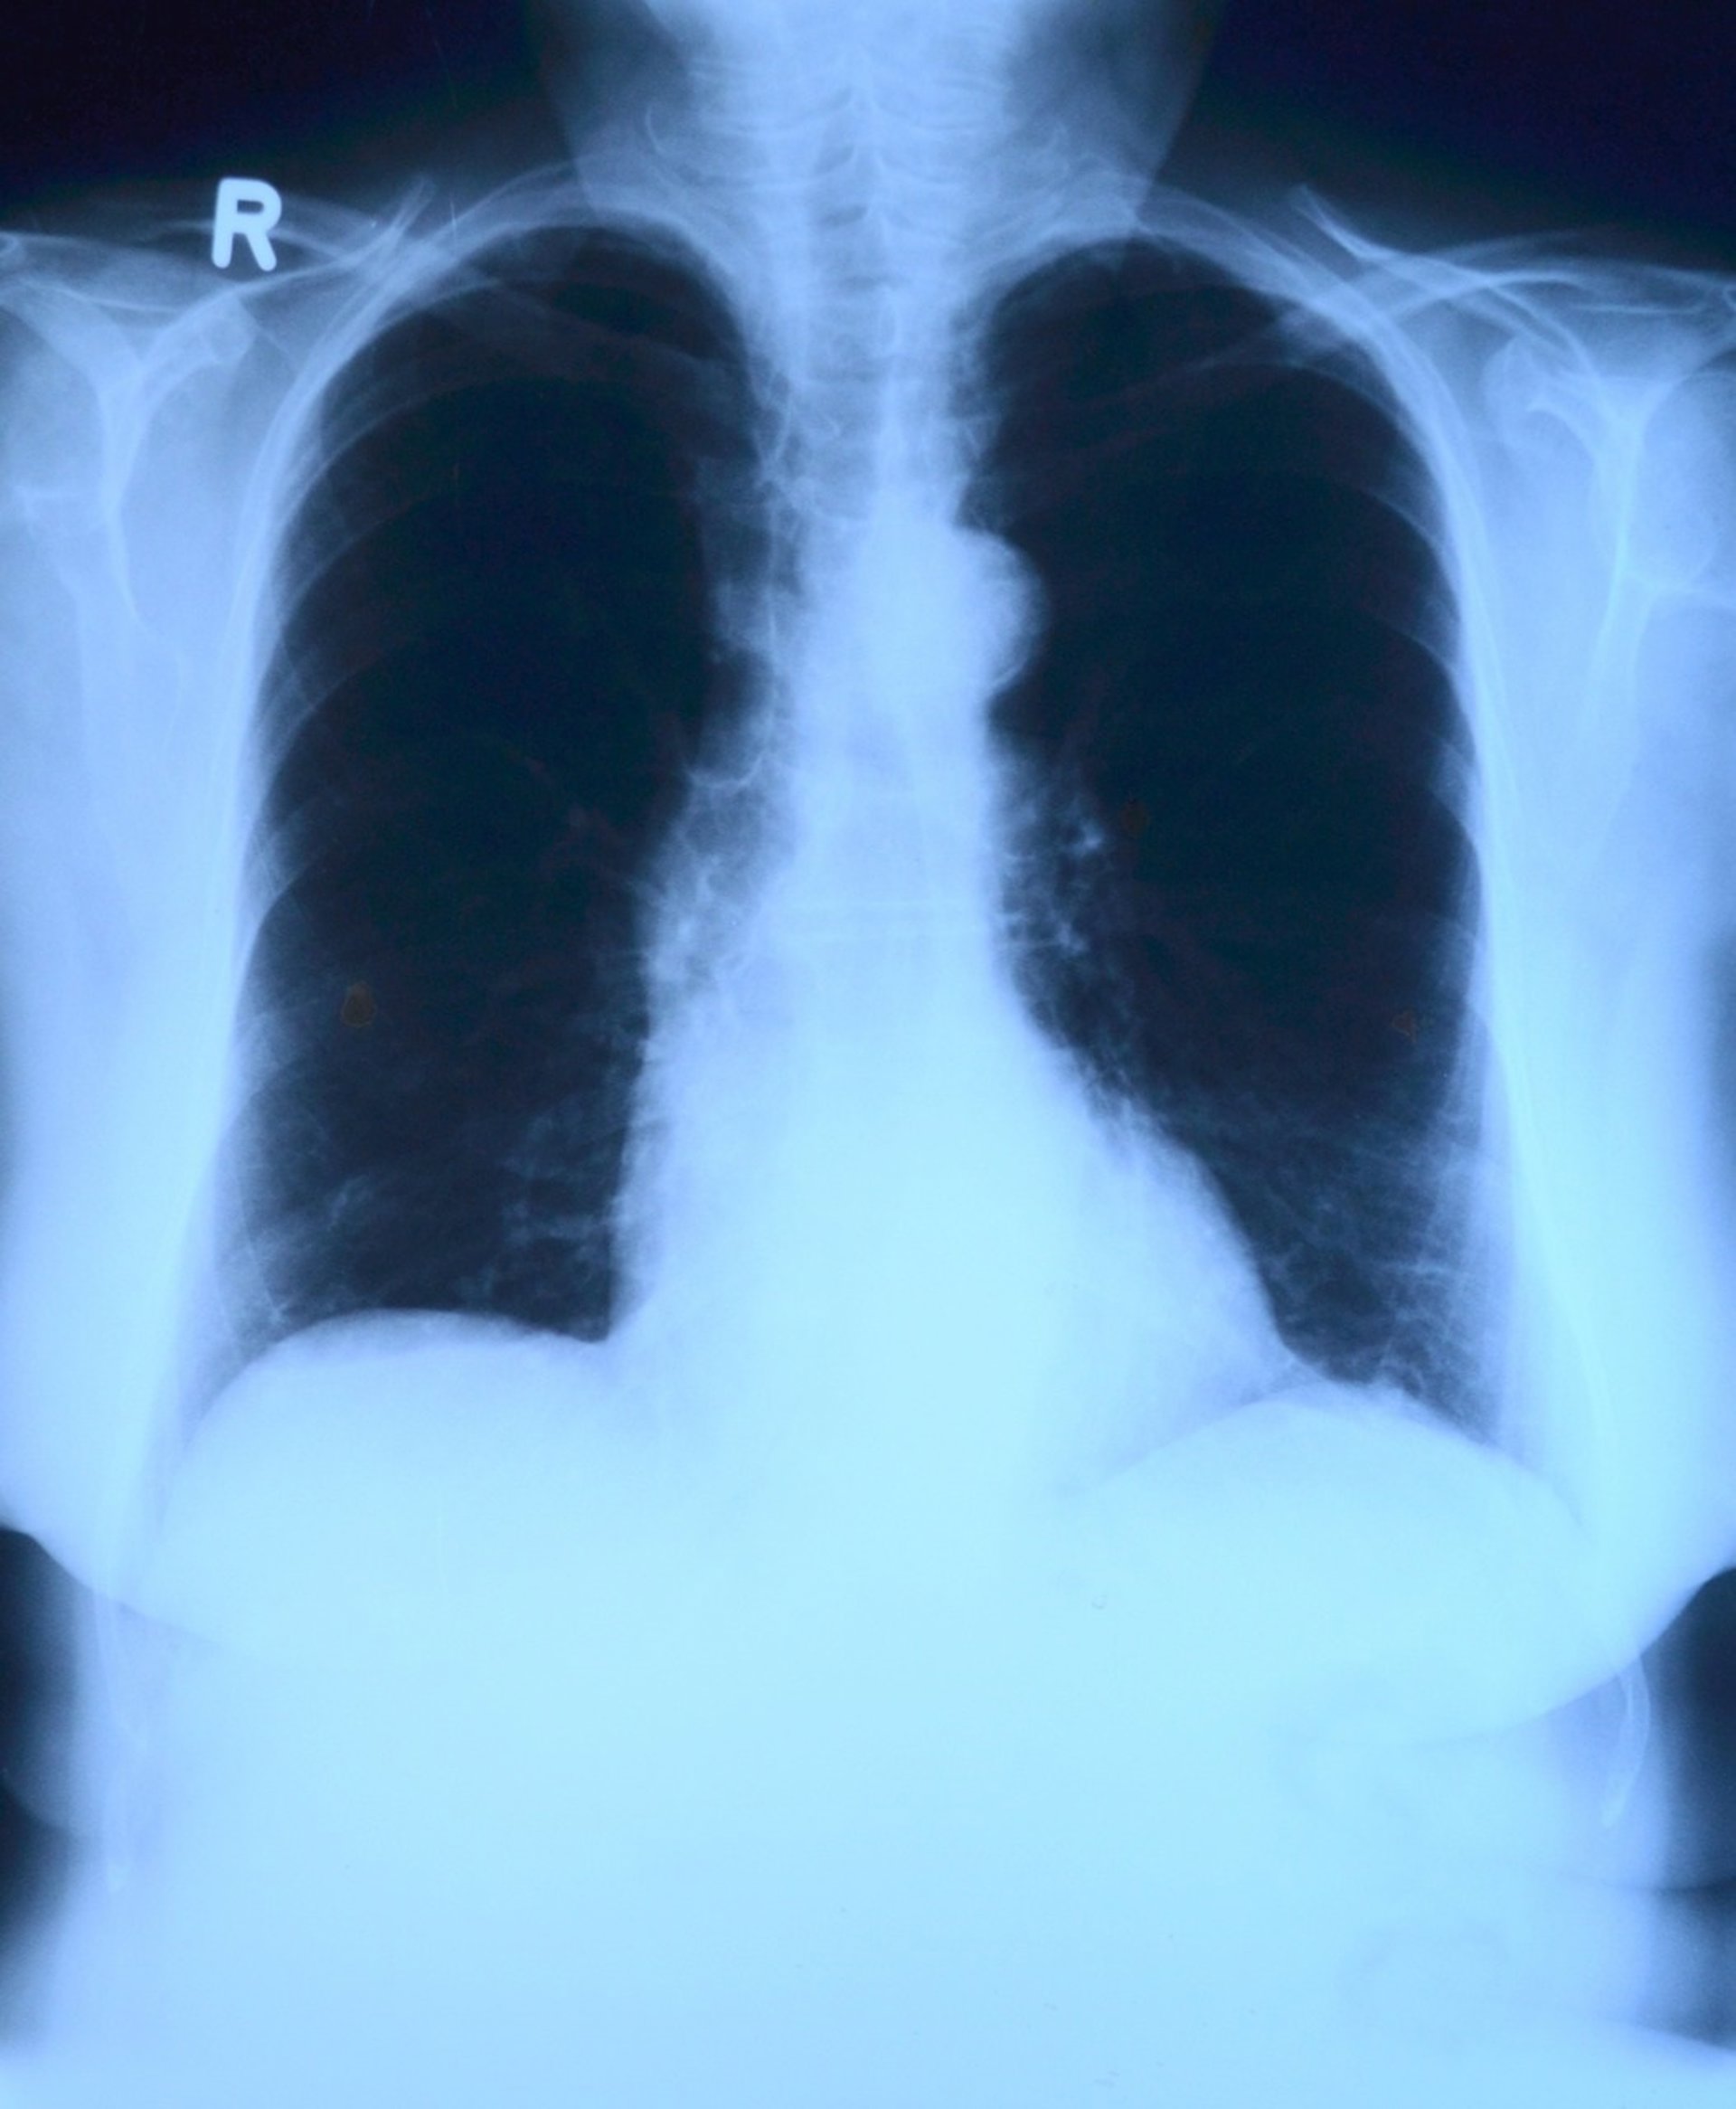

Una combinación de dos fármacos y radiación podría funcionar en ciertos cánceres de pulmón resistentes

A pesar de que el tipo más común de cáncer de pulmón --el cáncer de pulmón no microcítico (NSCLC, por sus siglas en inglés)-- ha visto recientemente importantes avances en el tratamiento de algunos subtipos genéticos, otros subtipos continúan evadiendo el tratamiento.

Aproximadamente, el 85 por ciento de todos los cánceres de pulmón pertenecen al tipo de NSCLC y, aunque ha habido algunos avances en el tratamiento de esta enfermedad, sólo el dos por ciento de los sobrevivientes viven cinco años más allá del tratamiento. Se han desarrollado fármacos para dirigirse a los subtipos de mutaciones en ALK y EGFR, y son en cierta medida eficaces, pero un subconjunto genético de NSCLC con mutaciones en los genes KRAS permanece resistente a las terapias convencionales y específicas.